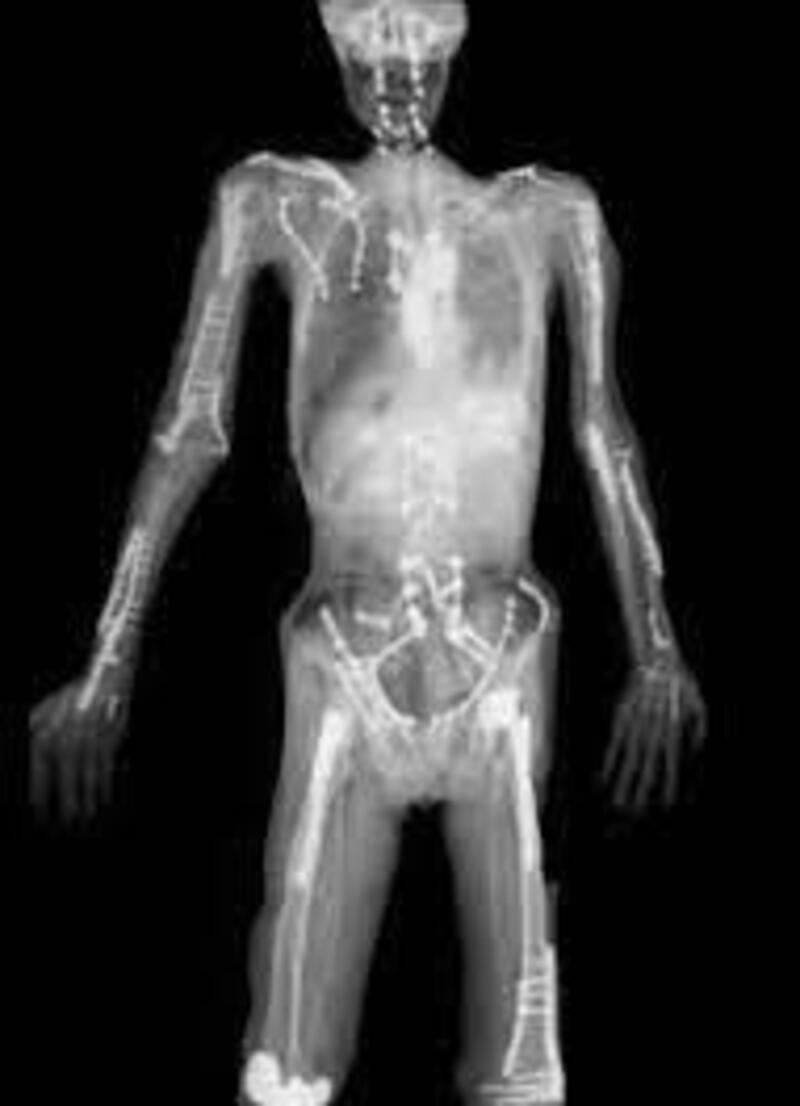

Dopo tutte queste peripezie, ecco però spuntare una radiografia di Pastrana: un’immagine che fa gelare il sangue. Piastre, viti, protesi, strutture interne… insomma, chi più ne ha più ne metta. Dal ginocchio ricostruito alle componenti di supporto per bacino e colonna vertebrale.

Insomma, il prezzo per diventare leggenda è caro e Travis pare averlo pagato con il proprio corpo. Letteralmente.